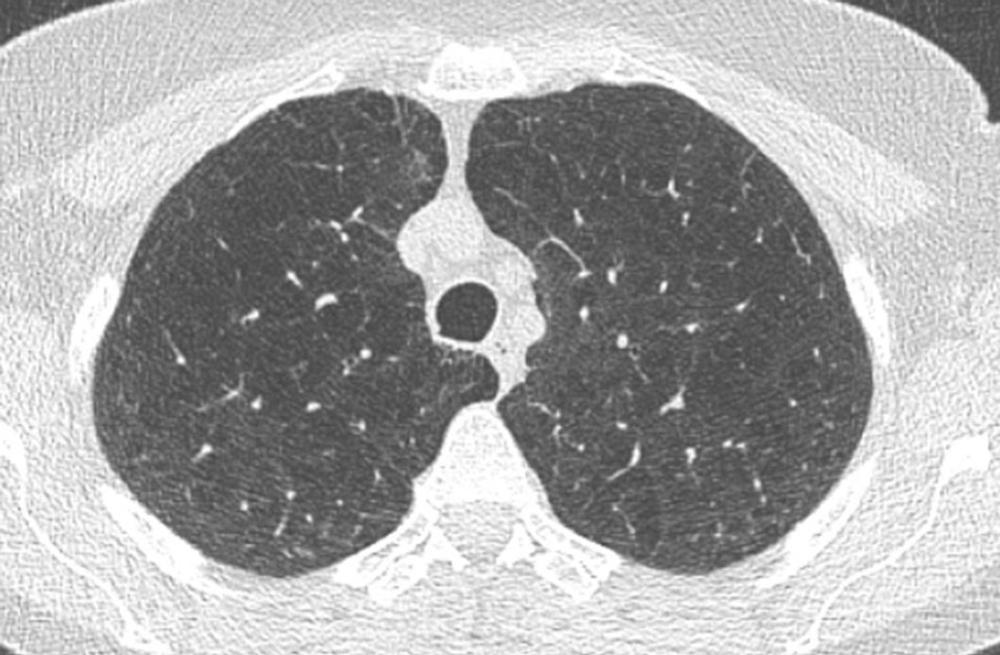

Figure 4. Image of lung showing emphysema.